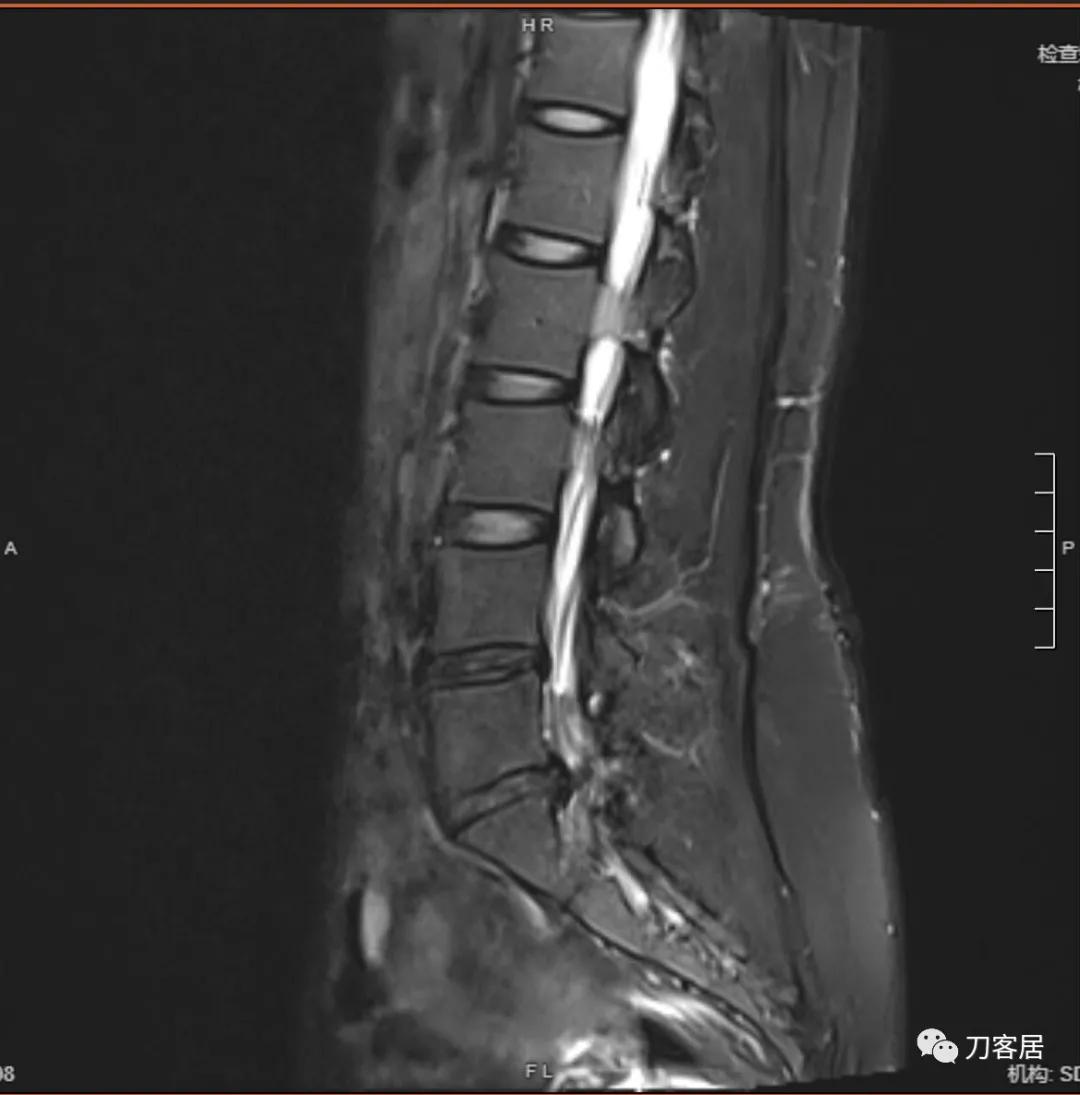

以下是患者的影像资料:

图2. 微创术前腰椎MRI矢状面T2相,提示腰5骶1椎间盘突出,腰5-骶1椎管内后方软组织结构紊乱,应该是以前做过手术。